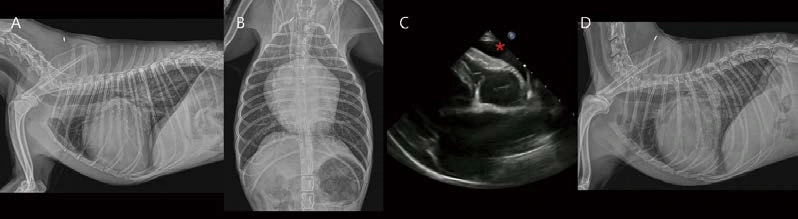

15살 중성화 암컷 2.71kg Maltese 환자가 호흡곤란으로 응급 내원하였습니다. 1년 전에 유선 종양 수술 병력이 있었습니다. 호흡수 108, 혈압 80, 심청진 시 muffled sound가 확인되었습니다. 흉부방사선 검사에서 폐엽 전반에 걸친 다수의 결절성 음영이 관찰됩니다. 또한 globoid cardiomegaly가 관찰됩니다. 심비대에 비해 폐혈관은 얇게 관찰되어 pulmonary hypoperfusion 상태가 고려됩니다(A, B). 폐초음파에서 다수의 폐 전이(균질한 저감쇠, 한계가 명료한 둥근 결절성 음영) 소견이 관찰됩니다(E, 화살표). 심초음파 검사에서 다량의 심낭수가 관찰됩니다(C, D, *). 심낭수로 인해 우심실, 우심방의 심한 collapse가 관찰됩니다. 심낭막에서는 부분적으로 불규칙한 결절성 비후 영역이 관찰됩니다(C, D, 노란 화살표). CVC plethora(F), splenic mass(G)가 관찰됩니다. 이미 유선 종양에 의한 전신 전이 상태로 생각되었으나, 심한 cardiac tamponade로 응급 상태였으므로, 수액을 공급하면서, 매우 낮은 속도로 조심스럽게 심낭수 천자를 실시하였습니다. 약 100ml의 혈액성 심낭수 천자를 진행하면서 환자는 호흡이 편해지는 듯하였으나, 갑자기 CPA 가 발생하였습니다. Atropine, epinephrine에 심박, 자발 호흡이 돌아왔으나, 혈압은 40mmHg였고, Dobutamine CRI, 수액 shock dose로 유지하는데, 혈압 30mmHg이 떨어지면서 다시 CPA 가 발생하였습니다. 삽관 이후 벤틸레이터를 유지하면서 응급 약물 처치하였으나, 반응이 없었고, 안타깝게도 심낭수 천자 이후 약 1시간 후 사망하였습니다.

Pericardial decompression syndrome은 post-pericardial drainage low cardiac output syndrome이라고도 합니다. 흔하지 않지만, pericardiocentesis 또는 pericardiostomy 이후에, 시술자가 iatrogenic trauma(cardiac puncture, pneumothorax, diaphragmatic injury 등)를 유발하지 않았음에도, 치명적으로 발생할 수 있는 complication입니다. 사람에서 다량의 종양성 심낭수 증례는 발생률이 더 높은 것으로 알려져 있습니다. 심낭수 천자 직후부터 약 48시간에서 shock with left ventricular failure, pulmonary edema without shock, shock associated with biventricular failure, shock associated with RV failure and non-cardiogenic pulmonary edema 등으로 나타날 수 있습니다 (Yougeesh Prabhakar, Amandeep Goyal, Nauman Khalid, Nitish Sharma, Raj Nayyar, David H Spodick, and Lovely Chhabra, Pericardial decompression syndrome: A comprehensive review, World J Cardiol. 2019 Dec 26; 11(12): 282–291). Hemodynamic, ischemic, autonomic 가설 등이 있으나, Pericardial decompression syndrome은 수의학, 인의학 모두에서 underreported 상태로 생각됩니다. 이 환자처럼, 특히 다량의 종양성 심낭수 환자에서 주의가 필요할 것으로 생각되며(그럼에도 불구하고, cardiac tamponade 환자는 pericardiocentesis를 반드시 실시해야 함), 증례와 경험을 공유하여, pericardial decompression syndrome의 병태생리학 및 예방 방법을 함께 찾아 나가면 좋을 것 같습니다.